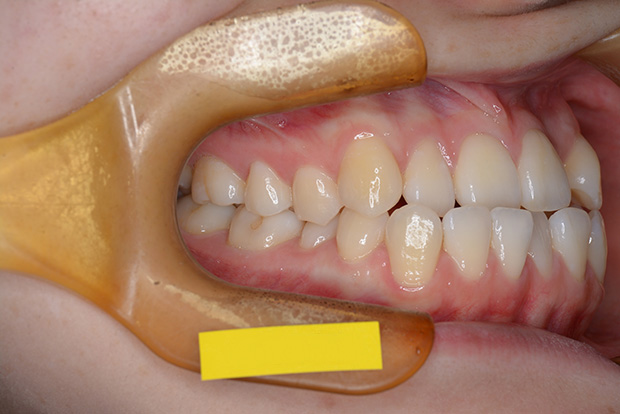

【ハーフリンガル】叢生 抜歯 上顎舌側マルチブラケット装置

| 主訴 |

ガタガタ |

||

|---|---|---|---|

| 診断名 |

右側Angle II級叢生 |

||

| 年齢 | 19歳 | 性別 | 女性 |

| 治療に用 いた装置 |

ハーフリンガル装置 (セミカスタム) | 抜歯部位 | 上顎両側第一小臼歯 下顎両側第二小臼歯 |

| 治療期間 ・回数 |

2年・24回 | 治療費 概算 |

約85万円 (調整料を含む) |

| 治療内容 詳細 |

歯科衛生科に入学し、自分の歯ならびが気になり始めたとのこと。上の歯列のみ舌側矯正(裏側矯正)、下は表側の、ハーフリンガルで治療を行いました。 |

||

| リスク・ 副作用 |

装置による違和感。疼痛、歯根吸収など |

||